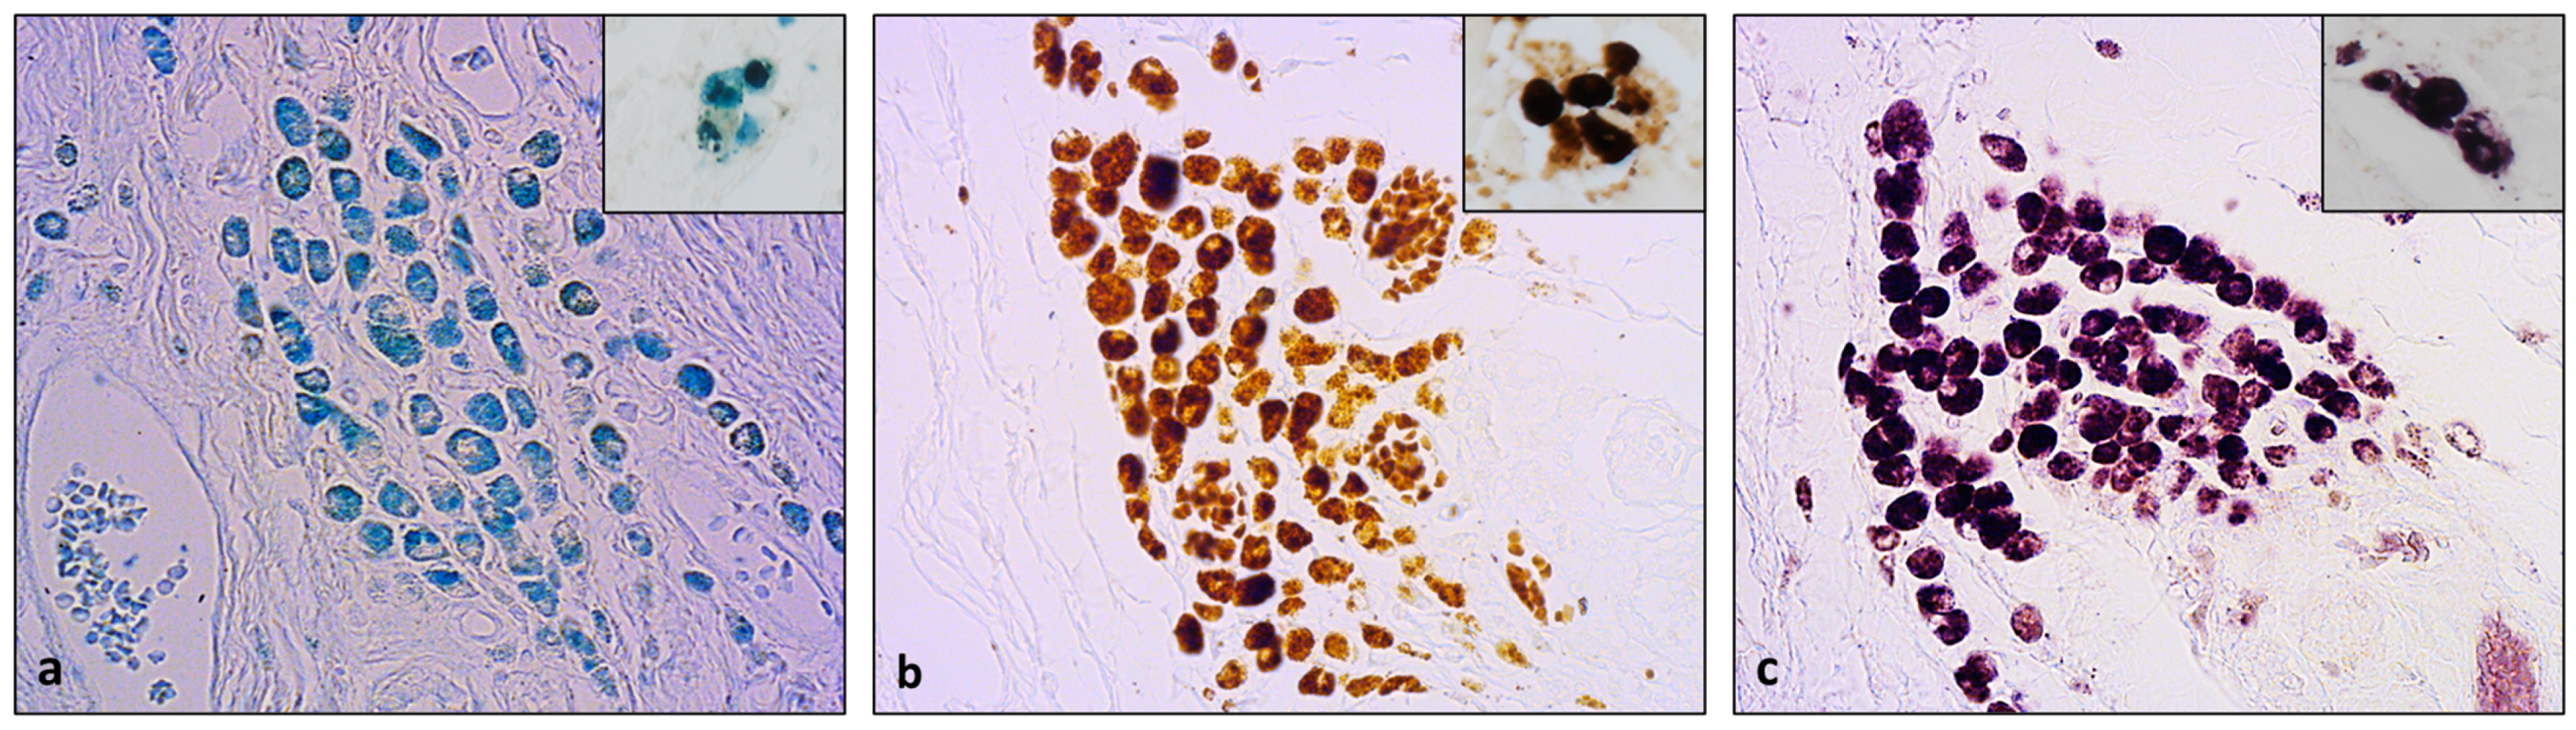

- Meguro, R.; Asano, Y.; Odagiri, S.; Li, C.; Iwatsuki, H.; Shoumura, K. Nonheme-iron histochemistry for light and electron microscopy: A historical, theoretical and technical review. Arch. Histol. Cytol. 2007, 70, 1–19. [Google Scholar] [CrossRef] [PubMed]